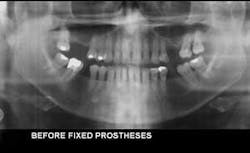

1. Panoramic radiographs. Panoramic radiographs are especially helpful for patient education, because the patient can easily orient the images to their own mouth. Digital panoramic radiographs are much better than analog panoramic radiographs for patient education. You can modify them in many ways (adding contrast, cropping, magnifying) to simplify the patient educational value.

3. Digital radiography. I strongly suggest incorporating digital radiography into your practice as soon as you can afford it (Figures 2 to 5). Although the initial digital images are not better than analog images, they can be enlarged, colored, textured, and have contrast changed, thereby increasing patient education potential and your diagnostic ability.